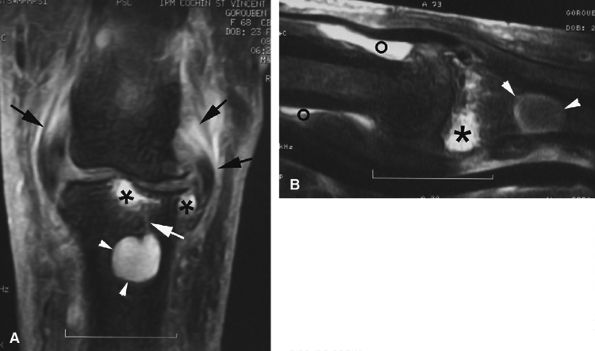

![]() |

FIGURE 11.142 ● Osteoarthritis of the PIP joint on (A) a coronal proton density fat-suppressed image and (B) a sagittal post-contrast fat-suppressed T1-weighted image. Erosive osteoarthritis with foci of subchondral bone edema (asterisks), a bone cyst (arrowheads), and capsuloligamentous thickening (black arrows) are seen. A possible thin channel between the cyst and the joint (white arrow) or diffuse synovitis (small circles) may also be seen.